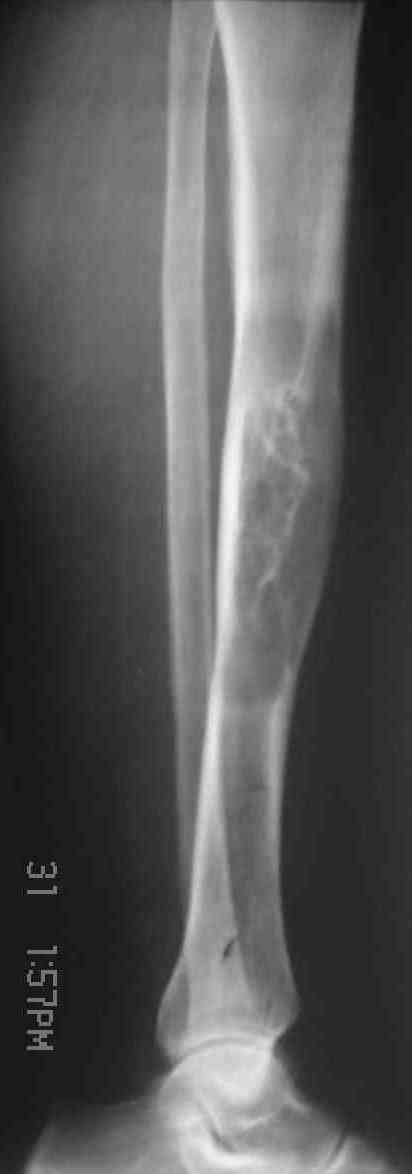

Я поддерживаю мнение доктора Odessky Jacob, что это образоавние возможно фиброзная дисплазия. Случай из моей практики - смотри рентгенснимки во вложении. Правда у моего пациента -полиосальная форма и болезнь проявилась в раннем детстве.

Доброго времени суток,уважаемые коллеги.Спасибо за помощь всем, кто откликнулся. Общий алгоритм понятен. Вот прямая проекция, извините за несвоевременность. С уважением, Алексей.

По представленным снимкам наиболее вероятен диагноз "фиброзная дисплазия".